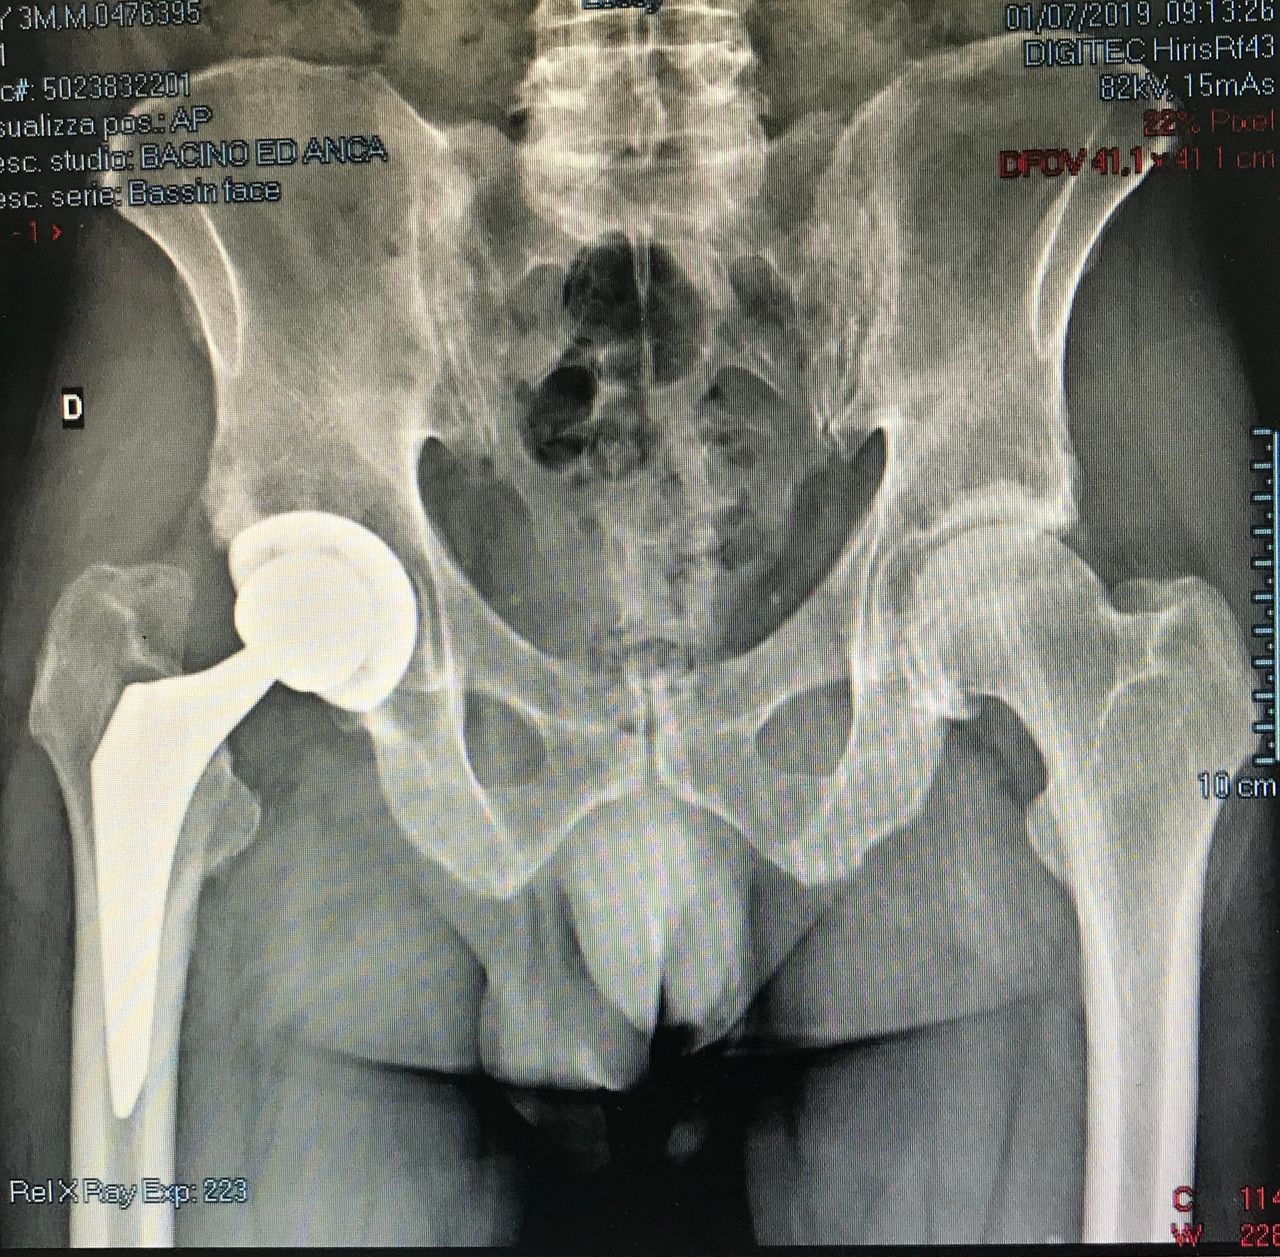

La protesi d’anca

• Ortopedia dell'anca